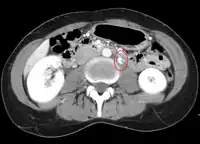

CT and MRI

CT and MRI can be used afterward to confirm compression by the AA and SMA with comprehensive measurements of the abdominal vasculature. A "beak sign" can often be seen in CT scans due to the LRV compression. However, CT and MRI cannot demonstrate the flow within the compressed vein. These two modalities can be used to confirm other evidence for NCS such as back-up of blood flow into the ovarian veins.[11][6]